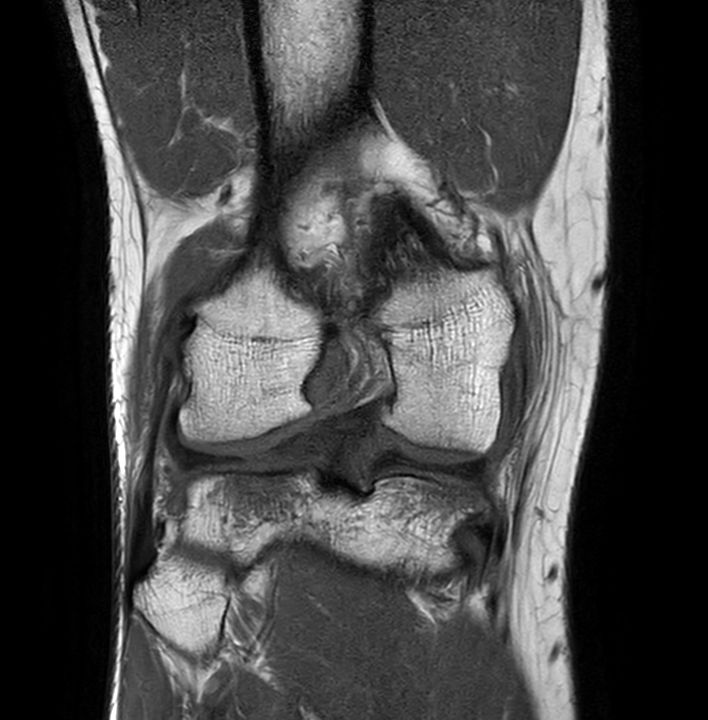

3D PDw TSE FatSat (coronal reformat)